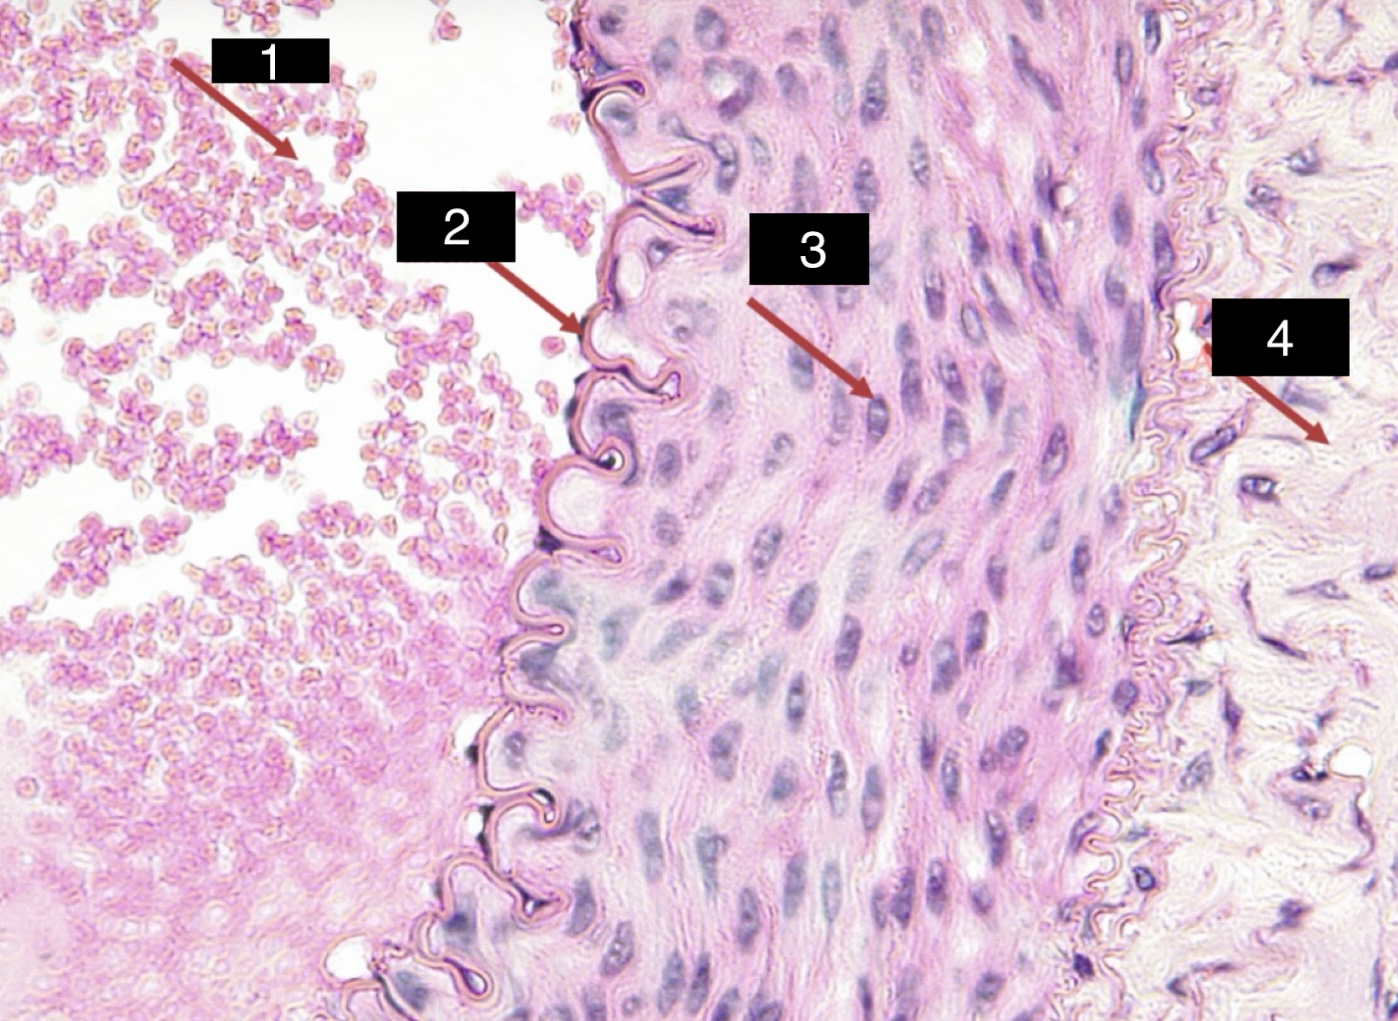

blood

erythrocytes

2

platelets

neutrophils

1

lymphocytes

monocytes